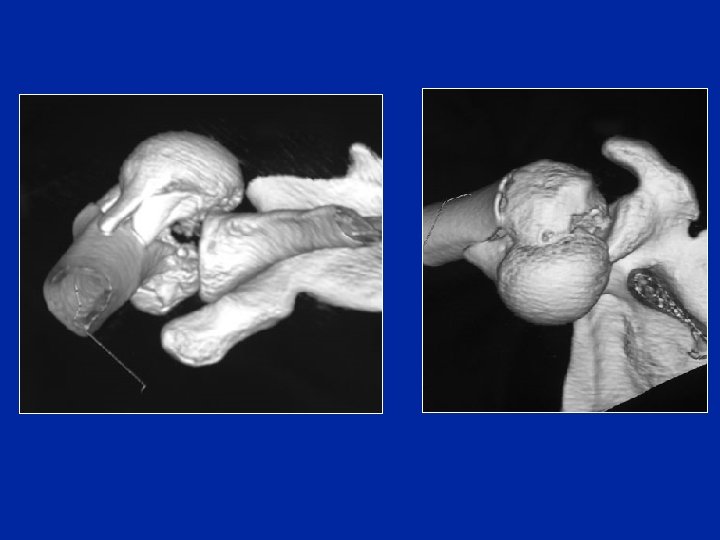

Fractures-luxations

Énucléation

Un cycliste tombe violemment sur le moignon de l’épaule. Il est très pâle mais conscient. C’est la première fois qu’il a un traumatisme de l’épaule. L’épaule est douloureuse et il est incapable de la mobiliser. Le membre supérieur est bloqué en abduction et rotation externe. A l’arrivée à l’hôpital l’épaule est tuméfiée et l’hématome qui est important gène l’examen clinique. La mobilisation passive de l’épaule est très douloureuse. Il existe une insensibilité du moignon de l’épaule. Les pouls périphériques sont perçus. Q 4 Quelle est votre conduite thérapeutique ? 1/ Si la radio ne montre pas de fracture du col huméral Réduction de la luxation (soit tentative de réduction lente, soit réduction sous AG) radio de contrôle 2/ Si la radio montre une fracture du col huméral Hospitalisation, bilan préop Réduction chirurgicale et ostéosynthèse de la fracture (plaque vissée ou clous élastiques) Immobilisation attelle 3 semaines puis mobilisation douce

Un cycliste tombe violemment sur le moignon de l’épaule. Il est très pâle mais conscient. C’est la première fois qu’il a un traumatisme de l’épaule. L’épaule est douloureuse et il est incapable de la mobiliser. Le membre supérieur est bloqué en abduction et rotation externe. A l’arrivée à l’hôpital l’épaule est tuméfiée et l’hématome qui est important gêne l’examen clinique. La mobilisation passive de l’épaule est très douloureuse. Il existe une insensibilité du moignon de l’épaule. Les pouls périphériques sont perçus. Q 5 Vous le traitez et pourtant son épaule devient raide et douloureuse dans les semaines suivantes, de même que son poignet alors que le moignon de l’épaule est redevenu sensible et non atrophié. Quelle complication secondaire vous évoque ce tableau ? Syndrôme épaule-main: algodystrophie du membre supérieur Phase chaude (pas de troubles trophiques)